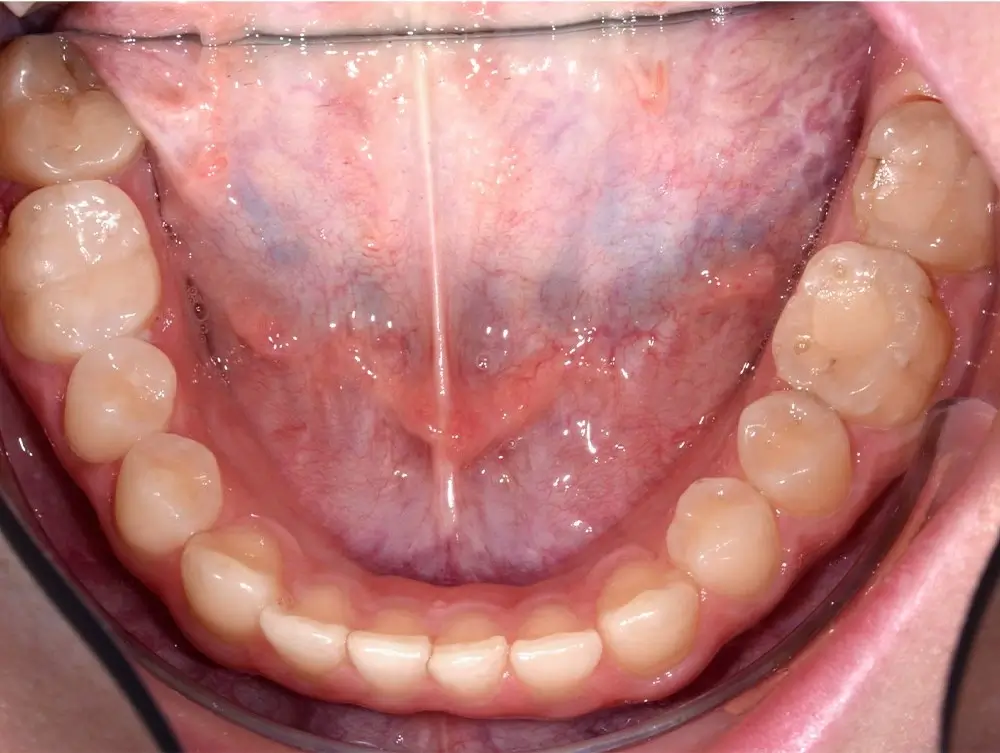

Открытый прикус - Кейс 2

Эффективность устранения дефекта прикуса посредством элайнеров FlexiLigner.

Результаты лечения